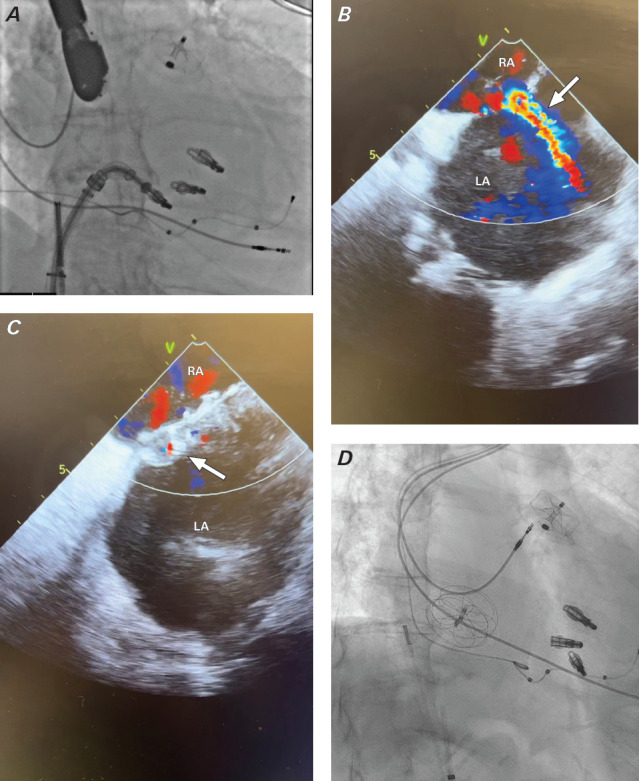

The evolution of percutaneous procedures that use transseptal puncture to treat left-sided structural heart disease has led to the emergence of iatrogenic atrial septal defects as a potential complication. These defects can result in hemodynamic decompensation and worsening clinical outcomes. Some iatrogenic atrial septal defects require immediate closure, others do not. This case report presents 2 patients who underwent transcatheter edge-to-edge mitral valve repair with transseptal puncture and required iatrogenic atrial septal defect closure (1 immediate and 1 delayed). The goal of this report is to highlight iatrogenic atrial septal defect assessment and the possible need for closure after transseptal puncture.